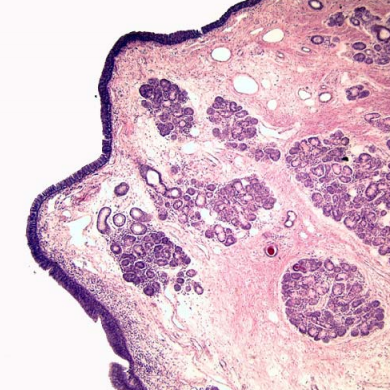

this is the larynx in the region of the ____

vestibular fold

2/ serous and mucuous glands

how do you know this is a vestibular fold of larynx?

respiratory epithelium with goblet cells and basal bodies